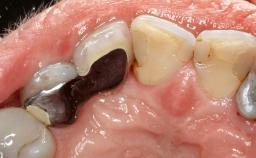

Late Presentation of Peri-Implant Mucositis Requiring Soft-Tissue Augmentation and Esthetic Crown Lengthening at Implant Site 11

Biological or technical complications around implant-supported prostheses place a significant burden on patients as well as the surgical and restorative team. Inflammation of the peri-implant soft tissues is often the first sign that something has gone awry. While there is never a good time for a complication, late presentation of inflammation in the soft tissues around a long-standing prosthesis triggers a period of research and review of the case in order to ascertain the treatment history and its possible contribution to the etiology of the situation. This becomes more complicated in situations where a patient has not received regular maintenance and clinical/radiographical examinations due to personal, financial, or professional reasons. When the complication occurs in the esthetic zone, the complexity of the situation expands exponentially, as the only acceptable outcome in the patient’s eyes will be the maintenance of the esthetics of the prosthesis.